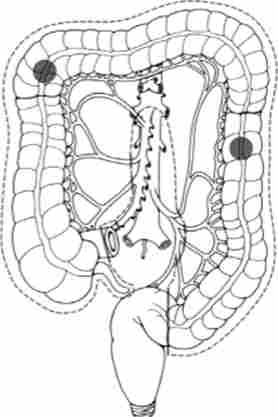

Найбільш часто рак розвивається в сигмовидної і сліпій кишці. Детально частота ураження різних відділів ободової кишки представлена на рис. 14.4.

Частота ураження карциномою різних відділів ободової кишки

Мал. 14.4. Частота ураження карциномою різних відділів ободової кишки